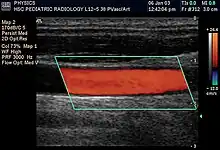

Doppler ultrasonography is used to study blood flow and muscle motion. The different detected speeds are represented in color for ease of interpretation, for example leaky heart valves: the leak shows up as a flash of unique color. Colors may alternatively be used to represent the amplitudes of the received echoes.

Doppler ultrasonography

Doppler ultrasonography employs the Doppler effect to assess whether structures (usually blood)[52][55] are moving towards or away from the probe, and their relative velocity. By calculating the frequency shift of a particular sample volume, flow in an artery or a jet of blood flow over a heart valve, its speed and direction can be determined and visualized, as an example. Color Doppler is the measurement of velocity by color scale. Color Doppler images are generally combined with gray scale (B-mode) images to display duplex ultrasonography images.[56] Uses include: